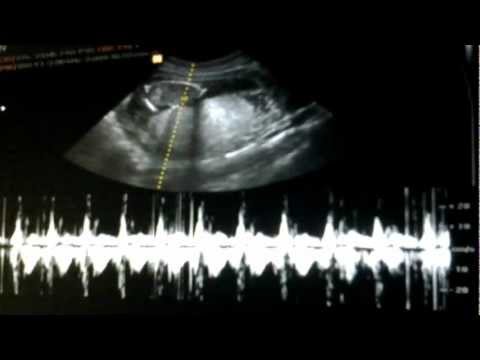

Foto Usg Janin 4 Minggu

Foto usg janin 4 minggu. Biasanya diikuti oleh pemindaian lain pada 18 21 minggu. Sebesar jeruk nipis panjang 5 4 cm dengan berat 14 g. Kehamilan 4 minggu 5 hari kehamilan 5 minggu kehamilan 5 minggu 2 hari five week pregnancy ultrasound with sac and yolk sac transvaginal ultrasound normal pregnancy at 5 weeks 2 days gestational sac black area and yolk sac are seen sac measures 6 25mm diameter yolk sac small white circle in left side of the sac yolk sac is a source of nutrients for the fetus the fetus is too small to be. Perkembangan janin 4 minggu 15 minggu melalui usg 2d.

Dalam kondisi yang normal ukuran kantong janin. Berikut adalah perkembangan organ tubuh janin di usia 4 sampai 8 minggu kehamilan menurut yates. Dihubungi terpisah dr sita ayu arumi spog dari rsu bunda jakarta menuturkan usg bisa digunakan sejak awal kehamilan yaitu usia kandungan 4 5 minggu untuk mendeteksi kantong kehamilan. Usg hamil 4 minggu.